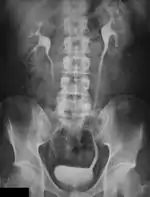

A selection of clinical applications of Digital Radiography are described in this chapter. General Radiography, being one of the mainstays of Diagnostic Radiography, has changed from a film-based imaging process to one based on digital technologies. The impact of these changes in terms of radiation dose and image quality are discussed in this chapter. Specialised applications such as Mammography, Digital Subtraction Angiography, C-Arm Computed Tomography, Multi-Detector CT, Dual-Energy Radiography and Image Fusion are also considered.

Digital Subtraction Angiography

Digital Subtraction Angiography (DSA), as the name implies, involves an image subtraction technique - see Figure 7.1. As will be seen below, the technique involves more than simply applying a subtraction process in the digital image processor. In addition, it will be seen that the type of technology utilised, while based on the design of fluoroscopy systems, needs to incorporate a number of modifications unique to DSA. Before addressing the technology however, some basic physics needs to be introduced which will aid in putting the subsequent technology discussion into context.